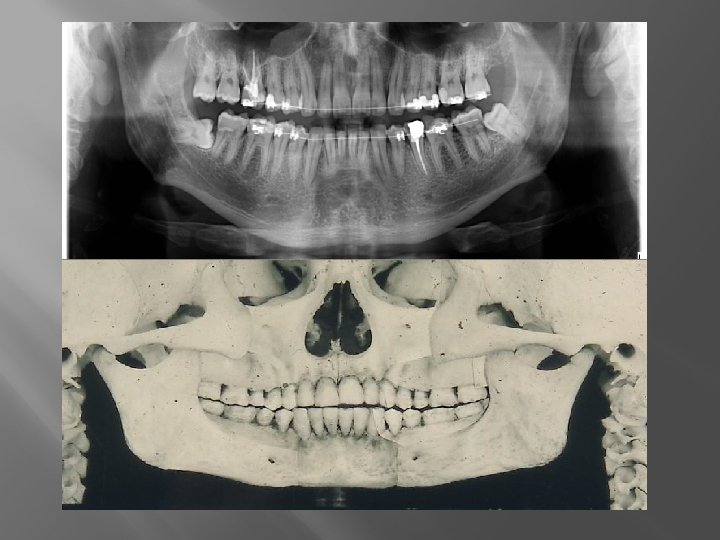

CBCT � � 3 dimenziós képalkotás A torzítás elhanyagolható � Mérés lehetősége � Sebészi sablonok � � A kórfolyamat pontos nyomon követhetősége. Jelentősebb sugárterhelés?